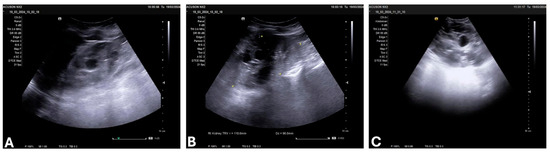

2. Materials and Methods

3.4. Laboratory Findings, Imaging, and Stage of ADPKD